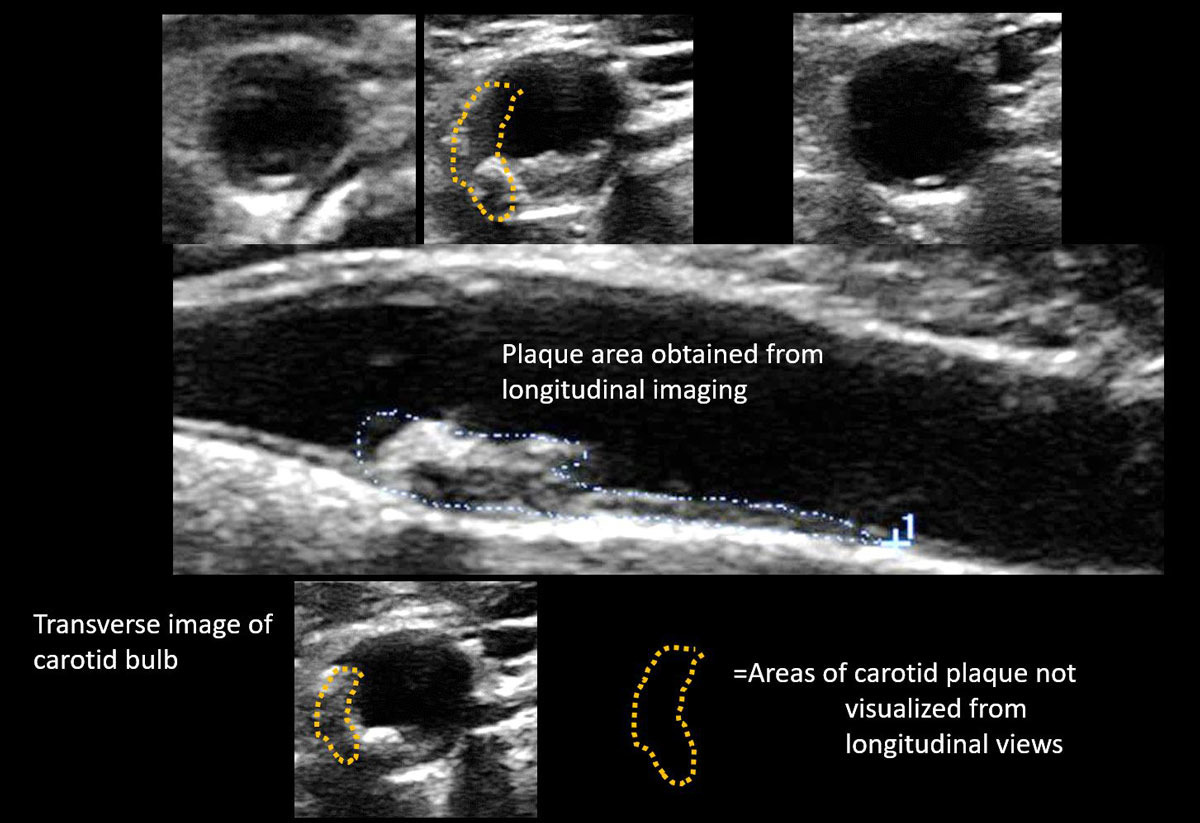

- 혈관 플라크(지방, 콜레스테롤 침착물)

플라크가 혈류에 영향을 줄 정도로 커지면 협착이 발생하고, 이 플라크 조각이 떨어져 나가 뇌혈관을 막으면 뇌경색이 발생할 수 있기에 조기 발견이 매우 중요합니다. 또한 IMT(혈관 내막-중막 두께) 수치가 정상보다 두꺼워진다면 심혈관 질환의 발병 가능성이 높은 것으로 평가됩니다. 즉, 경동맥 초음파 결과는 뇌뿐 아니라 심장 건강 상태를 간접적으로 나타내는 지표로도 활용됩니다. 특히 다음과 같은 상황에서 더 세밀한 해석과 대처가 필요합니다.

- 플라크 위치와 크기